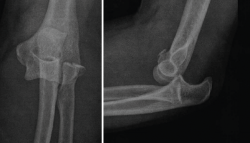

Figura 11. Radiografías de control en proyección anteroposterior y lateral en un paciente afecto de inestabilidad simple de codo persistente en el que se le realizó una reparación aguda del ligamento colateral lateral (LCL) y del ligamento colateral medial (LCM) mediante un sistema de arpones y suturas.

Típicamente, suele realizarse la reducción abierta mediante un abordaje posterior de codo o un abordaje lateral y medial combinado. En primer lugar, se aborda la zona lateral de la articulación del codo mediante un abordaje lateral de Kocher para realizar una inspección en busca de fragmentos óseos condrales o partes blandas interpuestas. El siguiente paso sería la reparación de LCL, el cual suele estar avulsionado de su inserción más proximal en el epicóndilo. La reparación típicamente se realiza mediante un sistema de anclaje con suturas, siendo importante también la posible lesión muscular de la región extensosupinadora. Una vez realizada la sutura de la zona ligamentosa y muscular lateral, se realiza una exploración bajo control escópico para evaluar la estabilidad del codo en rangos medios de movilidad y en posición de rotación neutra y pronación (evaluar la estabilidad del codo en supinación puede poner en riesgo la reparación del LCL). Si el codo sigue siendo inestable, entonces debe tenerse en cuenta realizar una reparación del LCM (Figura 10). Al igual que sucede con el LCL, la lesión del LCM suele localizarse en su inserción más proximal, aunque en ocasiones puede estar avulsionado del tubérculo sublime. La técnica de reparación empleada también suele ser mediante un sistema de arpón con suturas y, tras la realización de esta, deben repararse las lesiones asociadas en la musculatura flexopronadora (Figura 11). Si tras la reparación del LCL y del LCM, el codo sigue siendo inestable, debe colocarse un fijador externo de codo durante unas 4-6 semanas. Puede usarse, en función de las preferencias del cirujano, un fijador externo fijo o articulado.